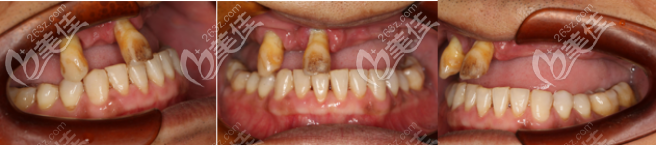

(術前牙齒狀況)

(術后效果)

(種植前后對比照片)